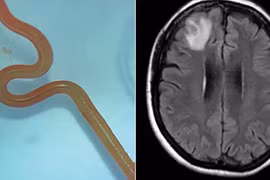

Ca đầu tiên trên thế giới lấy giun đũa còn sống nhiễm từ trăn khỏi não người

Các bác sĩ Úc đã lấy một con giun đũa dài 8 cm đang ngo ngoe khỏi não một bệnh nhân ở bang New South Wales. Đây là loài giun thường ký sinh ở loài trăn thảm.